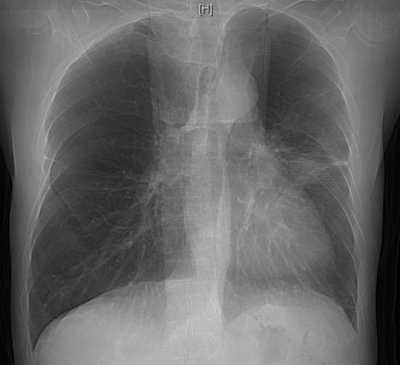

抱着最后一丝希望,李明章辗转至长沙市中心医院呼吸与危重症医学科救治。该科副主任朱锦琪、梁伟军及团队高度警觉免疫治疗病史可能带来的并发症,详细追溯他两年的免疫治疗用药记录,对其近期肺部CT影像进行反复对比和深入研判,认为其符合免疫检查点抑制剂相关肺炎(CIP)的典型表现,确诊其为迟发性、重度(4级)免疫检查点抑制剂相关肺炎。

明确诊断后,患者的治疗迎来关键转折点,团队迅速调整方案,启动大剂量糖皮质激素抗炎治疗,治疗效果立竿见影。患者的病情显著改善,氧合指数稳步上升,呼吸困难症状明显缓解。经过精心治疗,他在进入呼吸重症监护室一周后便转入呼吸科普通病房;10天后复查胸部CT,显示肺部弥漫性病变明显吸收好转,顺利出院。后续的定期随访复查也证实其肺部状况持续向好。